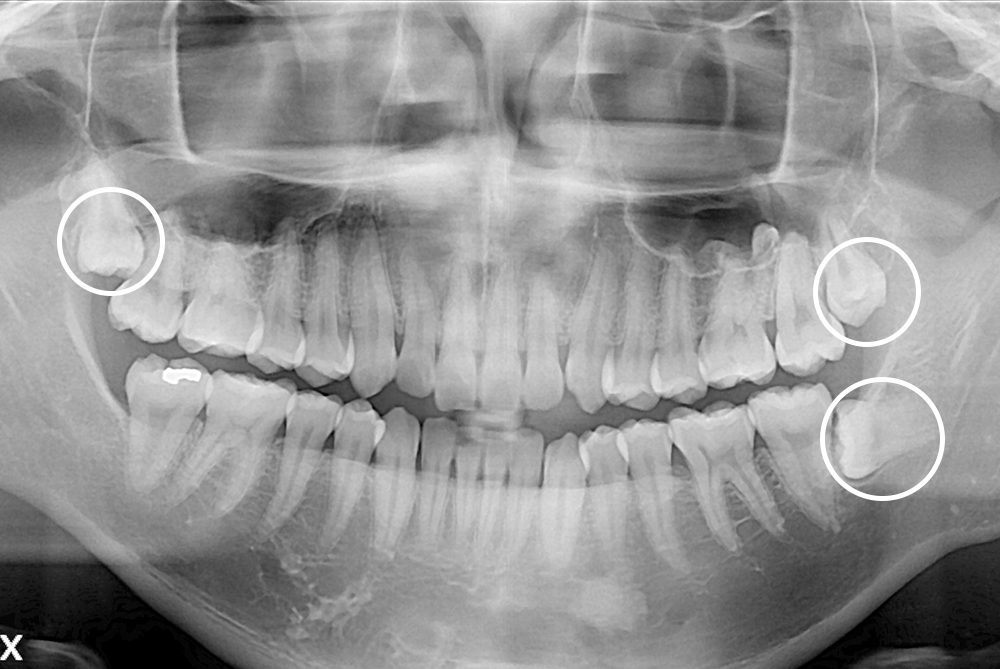

[사랑니] 매복 사랑니 발치

치료후 : 2020-01-30

세종치과는 구강악안면외과학 박사이신 원장님이 발치하는 치과입니다.